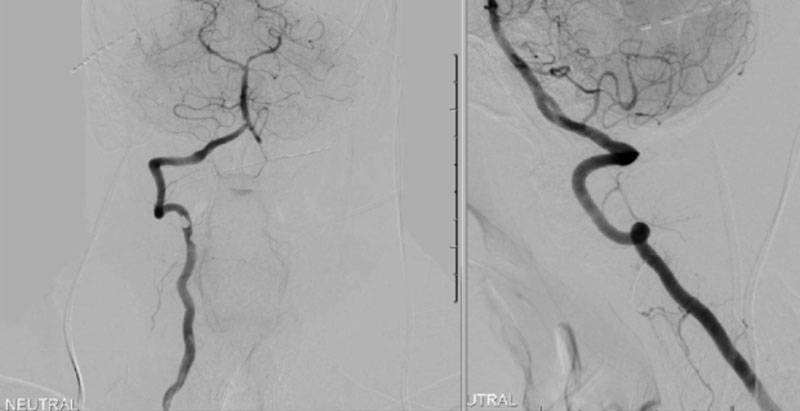

Dynamic provocative fluoroscopy failed to reveal significant Vertebral osseous instability (Figure 2A), however, Transcranial Doppler Flow velocities in the distal right Vertebral and Basilar Artery are markedly reduced during Extension of the Neck (Figure 2B).

On rotation to the left, the patient experienced mild symptoms, however no significant Vertebral Artery or basilar reduction in flow was observed. On rotation to the right, the patient experiences slightly more moderate symptoms, however no significant Vertebral Artery or vascular reduction flow was observed. On hyper extension of approximately 10-15 degrees, passively performed by the patient until symptoms are reproduced, angiogram demonstrates complete occlusion of the right Vertebral Artery at approximately the C2-C1 level. (Figure 5)